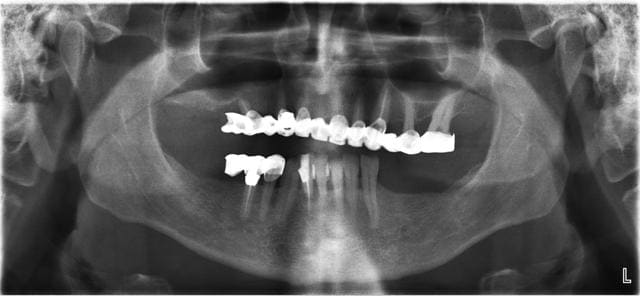

jeudi

extraction implantation mise en charge immédiate

mandibule

Pr  op e0j5ju - Eugenol

Utilisateur banni

20/03/2013 à 16h54

vendredi

maxillaire

Otp pr  op eyarzp - Eugenol

Wilson, sur l’image jointe il y a l’OTP pré- opératoire, les dents extraites, une modélisation 3D du site et l’OTP post-opératoire avec les implants et prothèses posée en 1 temps chirurgical.